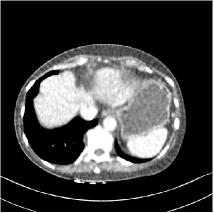

Fig. 3: Three examples (from top to bottom) of the reconstructed testing images using Momentum-Net with SimpleCNN (the second column), with SimpleCNN-RSN (the third column), and with Dn-RSN (the fourth column). The compared WavResNet denoised images are shown in the first column, and the reference images are in the fifth column. See their FBP images in Fig. 4.

Refer to caption

Fig. 4: FBP images of test examples.

Fig. 2 shows that the proposed Momentum-Net with SimpleCNN decreases RMSE dramatically in the first 30 layers, and tends to converge in 50 layers. The Momentum-Net reduces the mean RMSE value by 4.5 HU and gives smaller standard deviations in RMSE, compared to WavResNet, as reported in Table 1. This implies that the proposed Momentum-Net with SimpleCNN can improve both the accuracy and stability of low-dose CT image reconstruction than a state-of-the-art image denoising deep NN, WavResNet. The proposed Momentum-Net with SimpleCNN better removes noise and streak artifacts than WavResNet. It also provides clearer reconstructions of some details; see, in Fig. 3, the boundaries shown in the zoomed region at the top-right corner in the first example, the arrow pointed structures in zoomed areas of the second example, and the arrow pointed tissues in the left zoomed region in the third example.

3.3 Momentum-Nets involving RSN-based training

We show the reconstructed examples by Momentum-Net with SimpleCNN-RSN and Dn-RSN in the third and fourth columns of Fig. 3 respectively. Comparing the first three and the last columns in Fig. 3, we observe that Momentum-Net with SimpleCNN-RSN provides generally noisier reconstructions than WavResNet and Momentum-Net with SimpleCNN. However, Momentum-Net with SimpleCNN-RSN sometimes can provide clearer details than WavResNet. For example, in the right zoomed box of the second example, Momentum-Net with SimpleCNN-RSN shows better reconstruction quality for the arrow pointed structures than WavResNet, and in the left zoomed box in the third row, the former gives clearer small tissues marked by red arrows than the latter. Table 1 reports that Momentum-Net with SimpleCNN-RSN is approximately 2.9 RMSE (HU) higher than WavResNet, while it has smaller standard deviations. This implies that Momentum-Net with SimpleCNN-RSN is more stable than WavResNet, although it may not provide better image qualities. Momentum-Net with Dn-RSN, however, provides the worst visual and numerical results among the compared four methods in this paper.